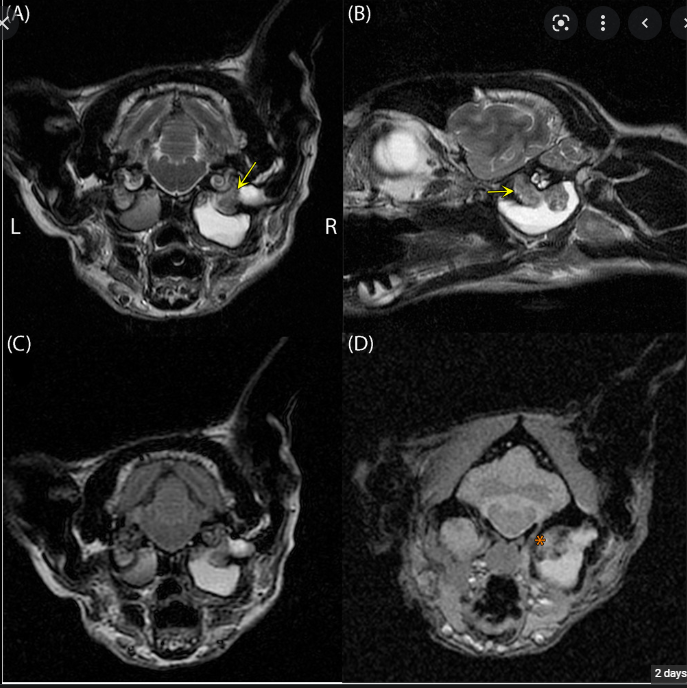

고양이 귀에서 생긴 진주종의 MRI 영상 특징

이번 논문은 이 진주종 환자를 MRI 촬영을 했을때 나타나는 특성에 대한 보고를 하는거이고